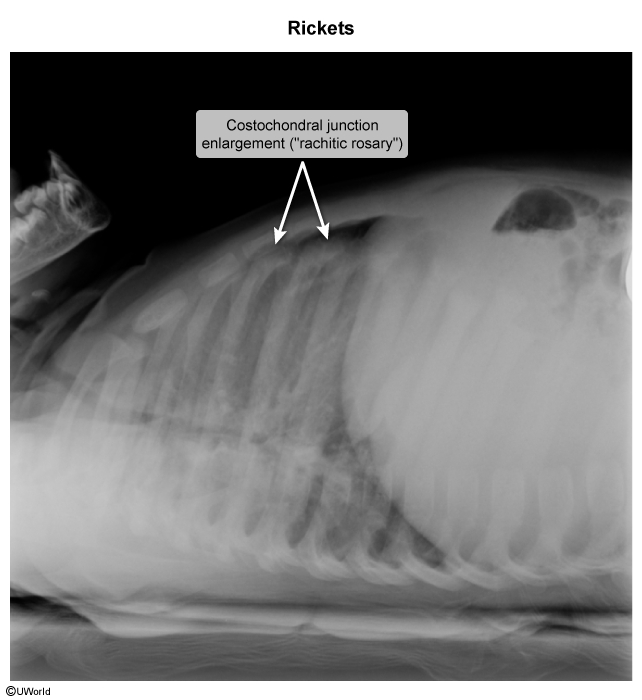

- Rachitic rosary (enlargement of the costochondral joints of the ribs).

- Rickets is usually diagnosed through radiographic (X-ray) examination of the long bones.

- Findings may include:

- Osteopenic bone shafts (low bone density).

- Widened growth plates.

- Frayed and cupped metaphyseal ends (irregular and blurred bone ends).